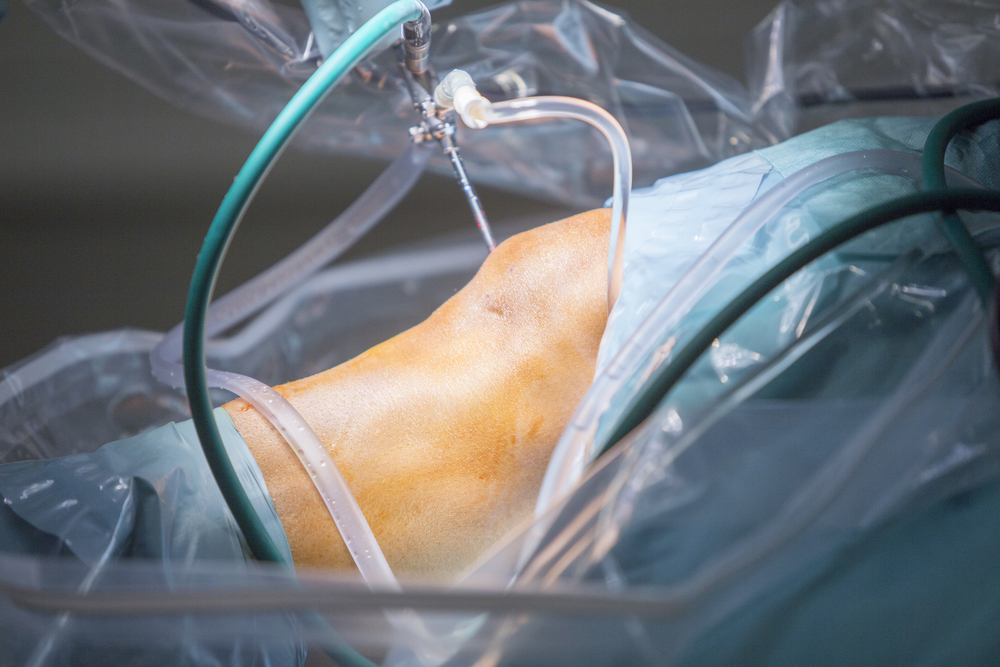

Después de que la anestesia haya sido aplicada, el cirujano hará pequeñas incisiones en la rodilla a través de las cuales bombeará solución salina para inflarla y lograr una mejor visibilidad.

Posteriormente introducirá un tubo estrecho con una cámara muy pequeña a través de una de las incisiones, de esta manera el cirujano podrá observar en la pantalla y diagnosticar el problema. En caso de que se requiera realizar algún tratamiento quirúrgico, el cirujano introducirá instrumentos diminutos a través de las incisiones para reparar la rodilla a través de cirugía artroscópica.

Finalmente el cirujano drenará la solución salina y cerrará las incisiones con suturas y las cubrirá con un apósito.

La artroscopia de rodilla suele durar entre 30 minutos y poco más de una hora.

Después de que la anestesia haya sido aplicada, el cirujano hará pequeñas incisiones en la rodilla a través de las cuales bombeará solución salina para inflarla y lograr una mejor visibilidad.

Posteriormente introducirá un tubo estrecho con una cámara muy pequeña a través de una de las incisiones, de esta manera el cirujano podrá observar en la pantalla y diagnosticar el problema. En caso de que se requiera realizar algún tratamiento quirúrgico, el cirujano introducirá instrumentos diminutos a través de las incisiones para reparar la rodilla a través de cirugía artroscópica.

Finalmente el cirujano drenará la solución salina y cerrará las incisiones con suturas y las cubrirá con un apósito.

La artroscopia de rodilla suele durar entre 30 minutos y poco más de una hora.